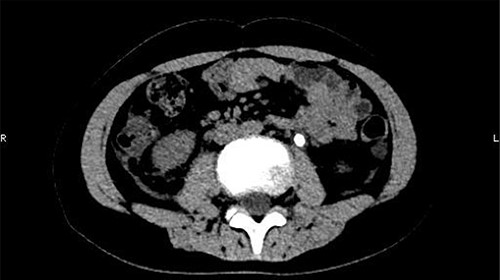

On 25 February, the patient complained of left back pain, nausea and vomiting. A further CT scan showed some irregular high-density shadows persisted in the left renal pelvis (Fig. 3) and an irregular high-density shadow was present in the left upper ureter (Fig. 4); furthermore, hydronephrosis was apparent in the left renal pelvis. There were no abnormalities in the bladder.

An irregular high-density shadow was present in the left upper ureter.